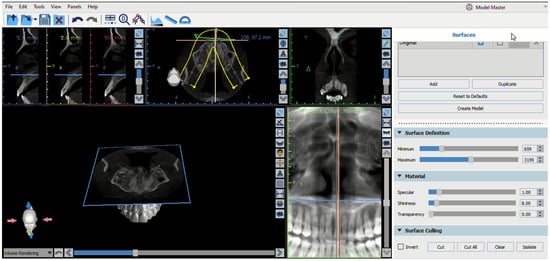

Digital Design of Juxta-Osseous Subperiosteal Implant Rehabilitation for Severe Maxillary Atrophy

Background: Rehabilitation of the severely atrophic maxilla remains a major challenge in implant dentistry, particularly when conventional endosseous implants and regenerative procedures are contraindicated due to extensive bone loss, sinus pathology, or patient-related factors. Advances in digital planning and additive manufacturing have enabled [...] Read more.

Background: Rehabilitation of the severely atrophic maxilla remains a major challenge in implant dentistry, particularly when conventional endosseous implants and regenerative procedures are contraindicated due to extensive bone loss, sinus pathology, or patient-related factors. Advances in digital planning and additive manufacturing have enabled the reintroduction of juxta-osseous subperiosteal implants as a graftless, patient-specific treatment option. This case report aimed to describe the complete digital workflow, surgical placement, and immediate prosthetic rehabilitation of a customized juxta-osseous subperiosteal implant in a patient with severe posterior maxillary atrophy and a history of failed sinus augmentation procedures. Case Presentation: A 75-year-old male patient presenting with left severe posterior maxillary atrophy and previous unsuccessful sinus lift surgeries was rehabilitated using a digitally designed, additively manufactured titanium subperiosteal implant. Cone-beam computed tomography–based planning and CAD–CAM technology were used to design a patient-specific framework, which was rigidly fixed to stable maxillofacial support and immediately loaded with a screw-retained provisional prosthesis. Results: Clinical and radiographic follow-up demonstrated stable implant fixation, soft tissue healing, absence of biological or mechanical complications, and satisfactory functional and aesthetic outcomes. The patient reported high levels of comfort and satisfaction throughout the treatment period. Conclusions: Digitally manufactured juxta-osseous subperiosteal implants may represent a predictable and minimally invasive graftless alternative for selected patients with severe maxillary atrophy, particularly when conventional implant placement or extensive bone augmentation is not feasible. Accurate digital planning, rigid fixation, and appropriate patient selection appear to be key factors for clinical success. Full article

Show Figures

Figure 1